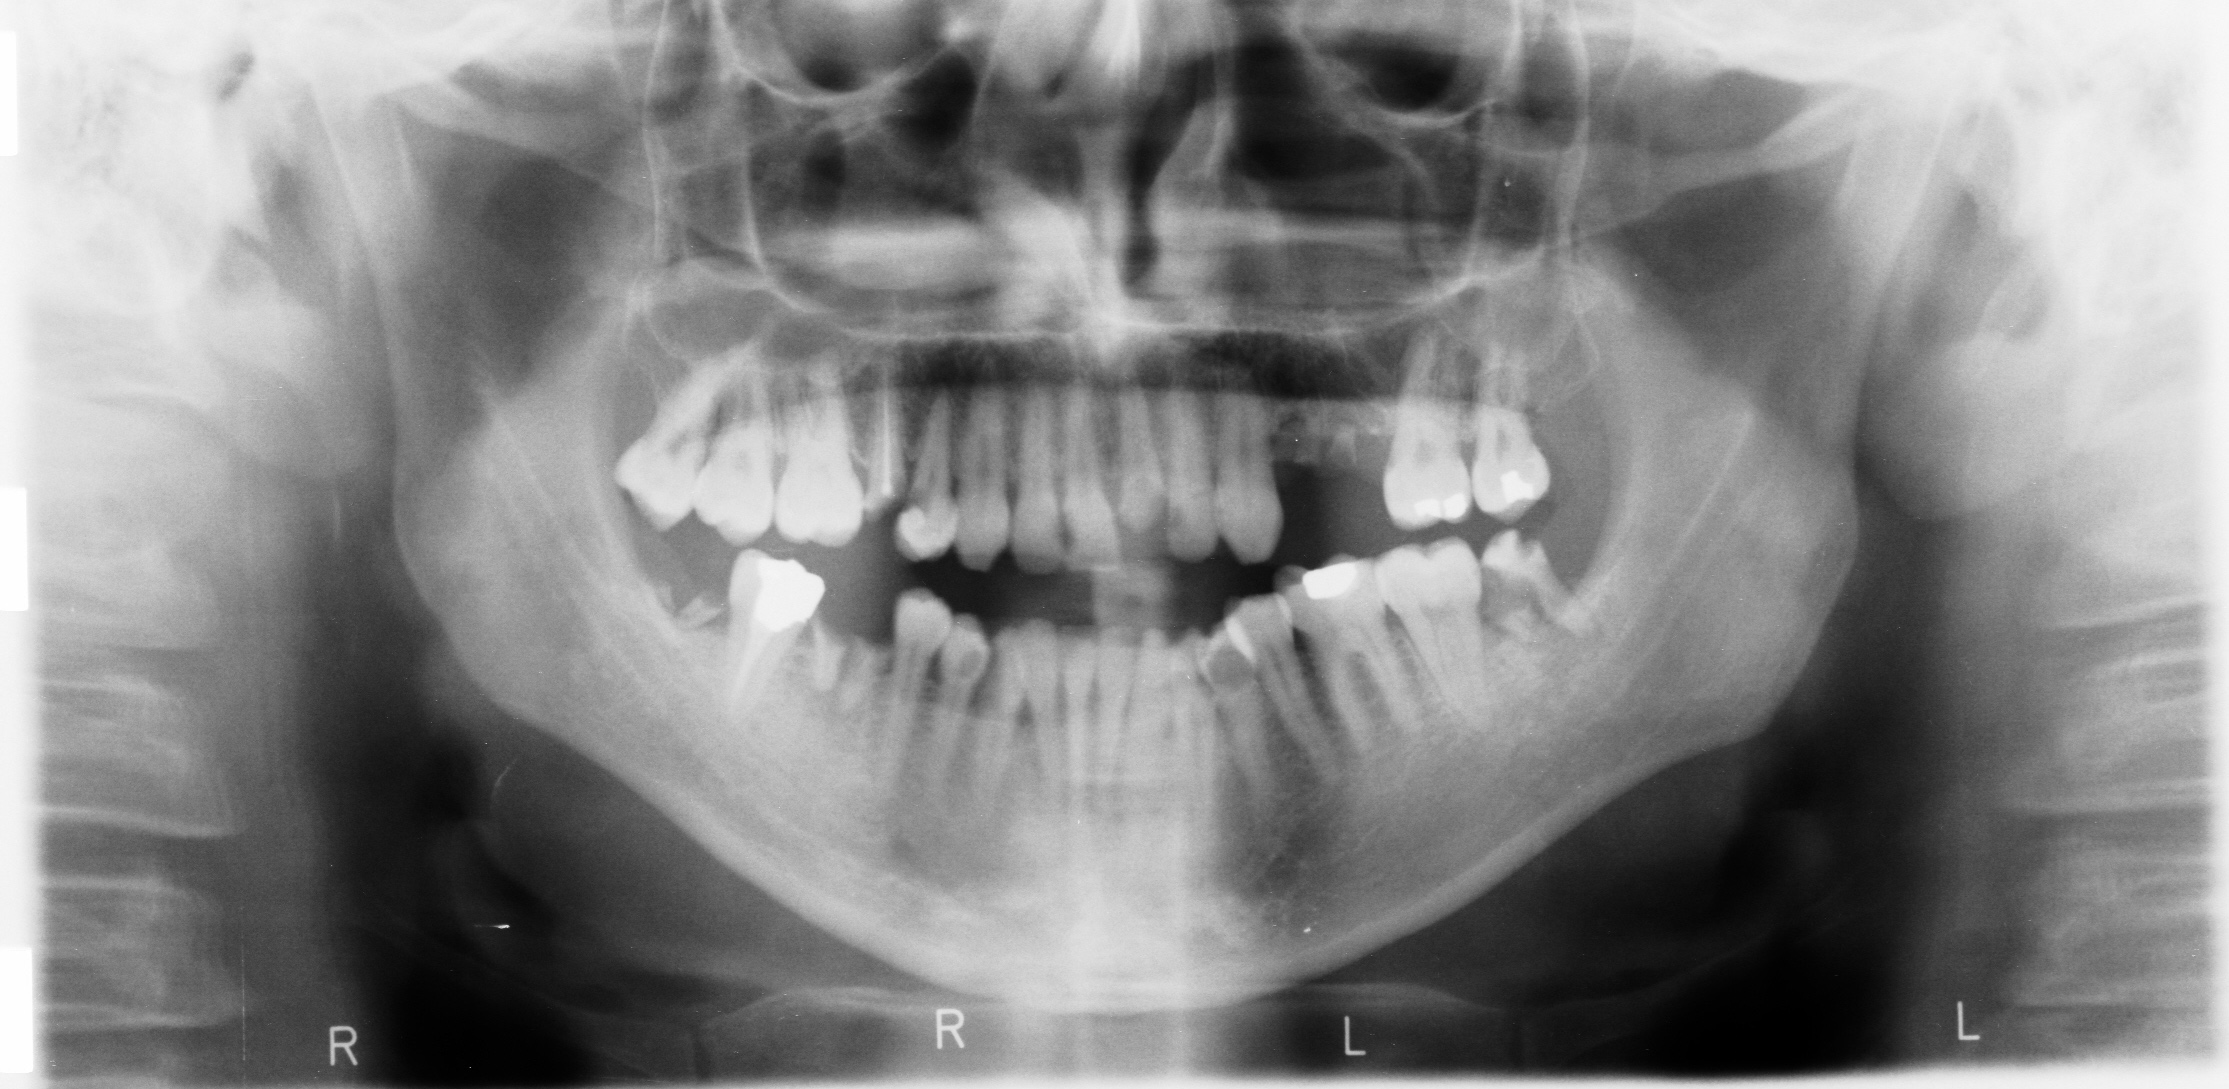

КТ лицевого скелета. Патоморфологически подтвержденный плоскоклеточный рак альвеолярного отростка нижней челюсти справа с дефектом костной ткани.